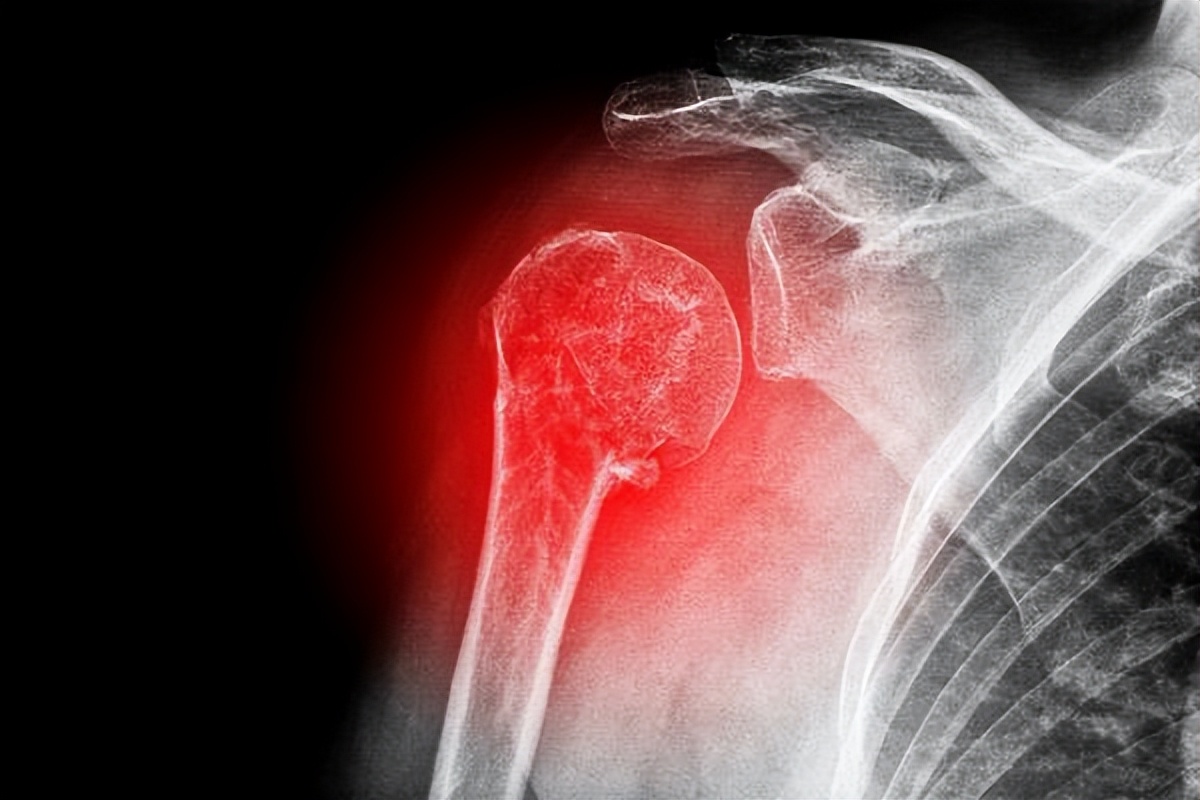

发生骨转移的时候要着重两点治疗方向,第一防止病理性骨折,如果一旦椎体骨折会造成瘫痪,对于患者的生活质量影响很大。

第二点处理好骨转移带来的疼痛,因为很多时候骨痛剧烈是患者难以忍受的,所以要提前做好准备。对于存在疼痛的患者,可以中西药联合止痛,在很大程度上疼痛是可以控制的。